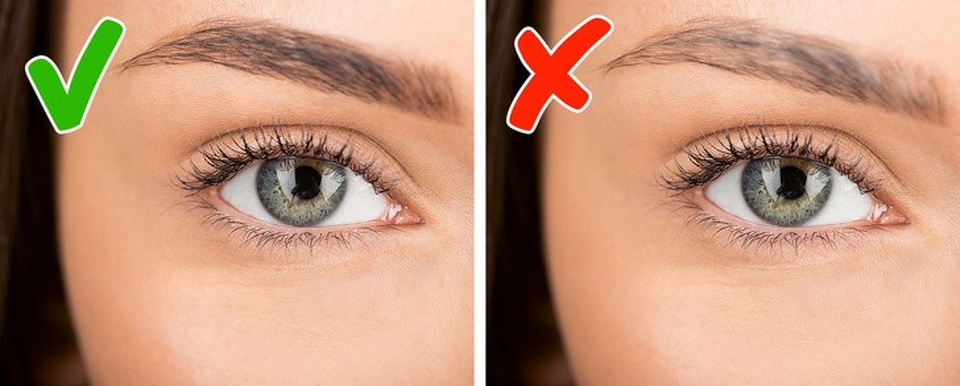

2. Rụng lông mày

Lông mày dày là một chỉ số sức khỏe quan trọng. Lông mày rụng định kì là hiện tượng khá bình thường nhưng nếu bạn nhận thấy lông mày đang bị rụng quá nhiều, xuất hiện khoảng hói ở lông mày thì hãy liên hệ ngay với bác sĩ. Triệu chứng này liên quan đến mức độ hoạt động của tuyến giáp quá mức hoặc không đủ.